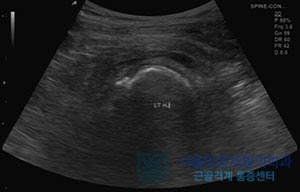

정기적인 건강 체크

정기적인 병원 방문과 검진을 통해 고관절 상태를 모니터링하는 것이 중요합니다. 조기에 발견된 문제는 조기에 치료할 수 있기 때문에 큰 문제로 발전하지 않도록 주의해야 합니다.